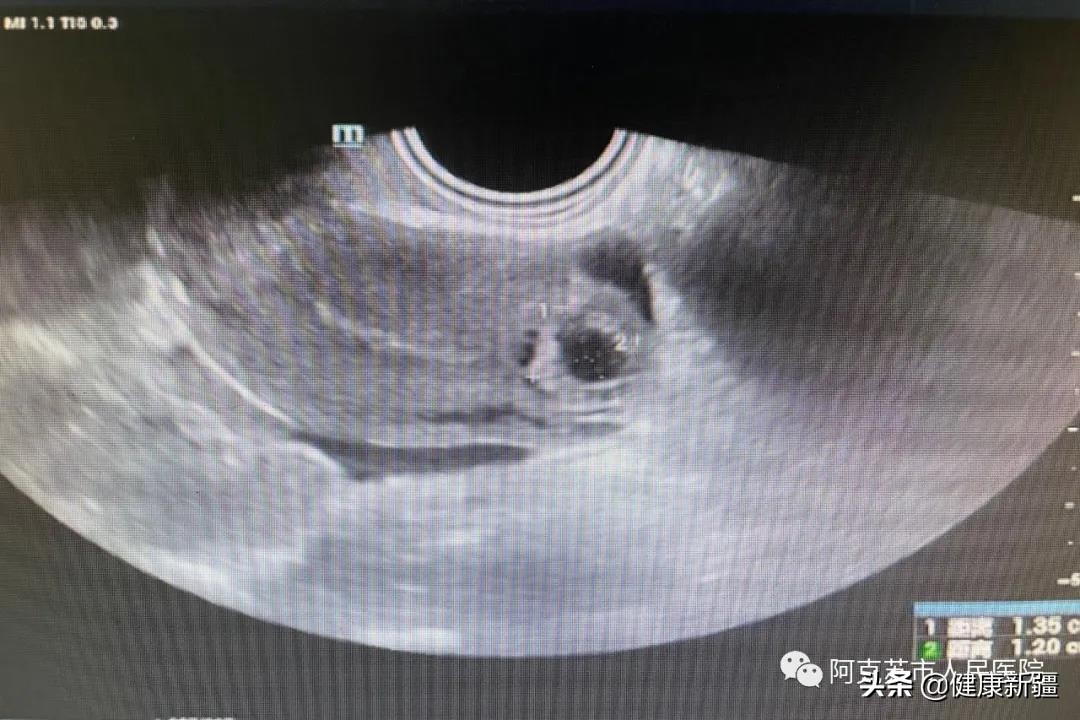

手术前

今年34岁的小刘,因为月经推迟来阿克苏市人民医院检查,经医院超声科医生检查后,发现小刘左侧宫角区无回声团,考虑患者应为输卵管间质部妊娠(异位妊娠)。一般情况下,异位妊娠需要采取外科手术进行治疗,但由于小刘患病部位的管腔比较狭窄且血管丰富,实外科手术难以止血,如处理不及时,随着胚胎的继续生长还容易发生破裂、大出血、休克等。